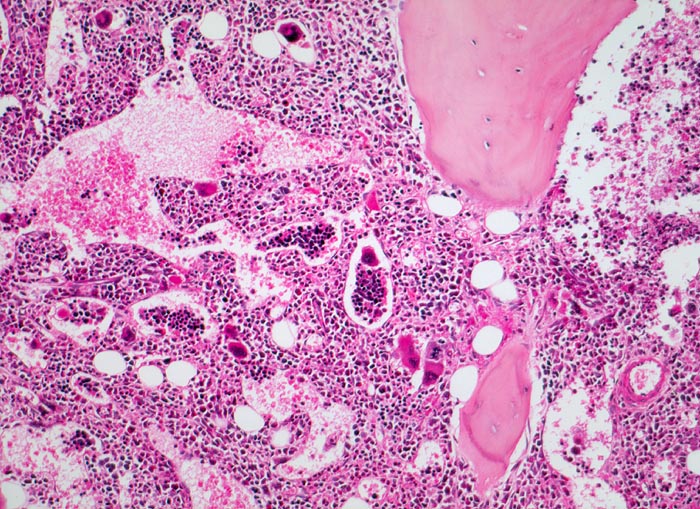

Primäre Myelofibrose (PMF)

Knochenmark, Beckenkamm

Hyperplastisches Mark mit fast vollständiger Verdrängung des Fettmarks. Typisch ist der Nachweis von Blutbildungsherden und Megakaryozyten in erweiterten Marksinus.

Splenomegalie, leichte Anämie, Leukozytose und Thrombozytose festgestellt bei einer Routineuntersuchung bei asymptomatischer Patientin.